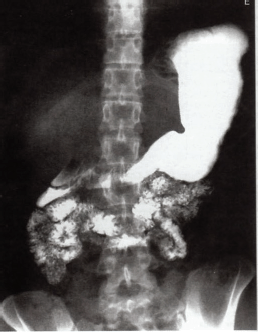

Considerando os exames radiográficos do sistema gástrico, observe a imagem a seguir e assinale a alternativa correta.